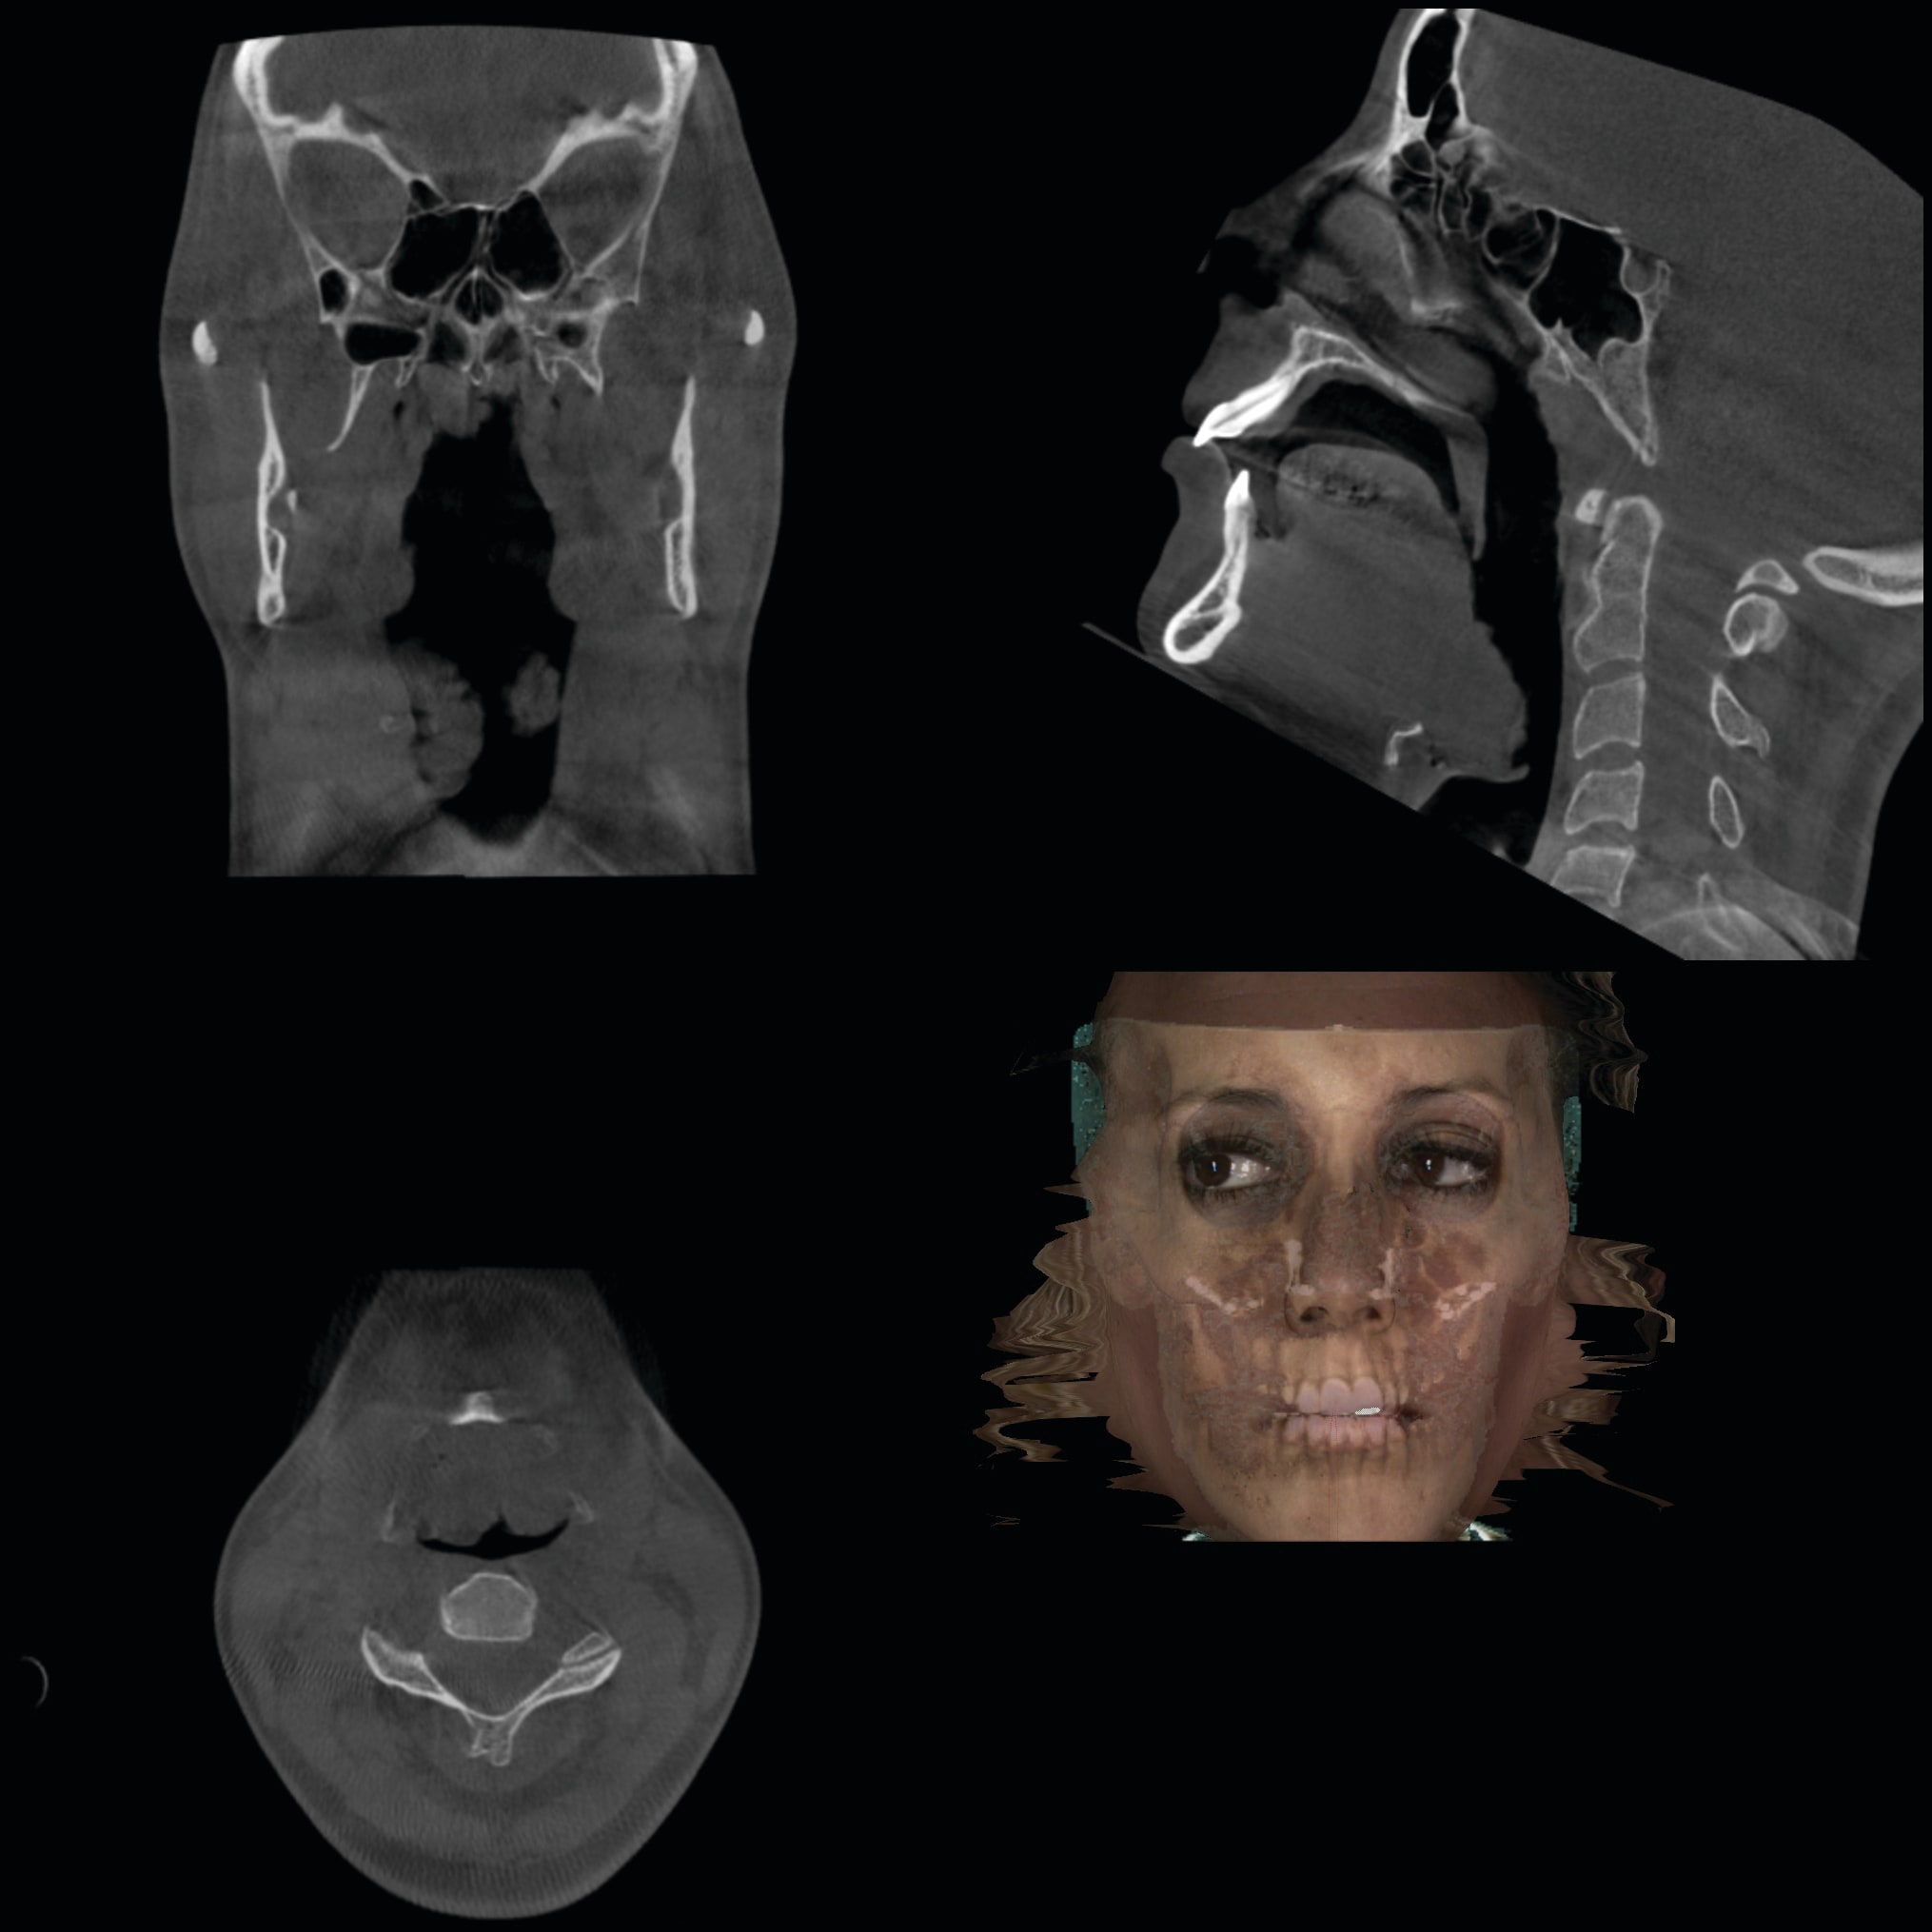

2. Any patient needing orthognathic surgery should receive a scan. The scan is certainly more diagnostic in all three planes of space than a 2-dimensional cephalometric image. Many oral surgeons can now use this scan to send to medical modeling companies for the construction of the splints used during the surgery. Not to mention the three planes of spaces gives the orthodontist a better perspective of the problem list prior to treatment planning and pre-surgery orthodontics. The models that are either acquired by a scan or with plaster models are incorporated in the patient’s 3D scan. The medical modeling companies can then do the surgery digitally and use the 3D models to make the surgical splints. These DICOM images give the orthodontist a more accurate visual treatment objective prior to treatment as the digital surgery gives the oral surgeon a thorough perspective of pre-surgical planning. The patient illustrated in Figure 4 through Figure 6 shows different type of images that can be generated from a set of DICOM images. With an exposure of only 14 mSv, the orthodontist can attain a pan, a ceph, and many different types of 3D images from the 3 simple planes of space to 3D images. Final records were acquired with an additional scan totaling another 14 mSv.